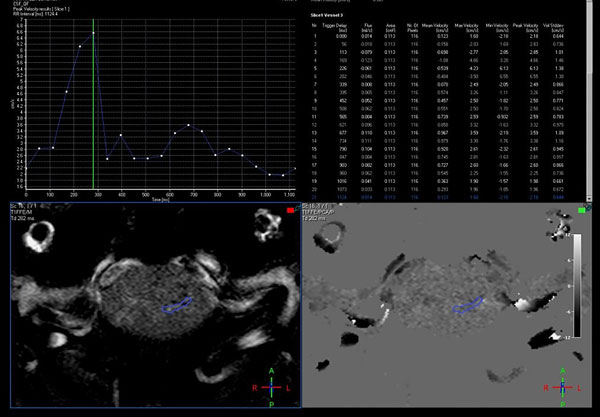

Estas secuencias permiten una evaluación cualitativa con valoración subjetiva del pasaje del LCR a través de las cisternas (Figura 1) y una valoración cuantitativa de la velocidad (Figura 2). La adquisición de las mismas se realiza de forma coordinada con el latido cardíaco (gatillado mediante el censado por el electrocardiograma o curva de pulso).13

La valoración cuantitativa requiere un postproceso para medición de flujo en estaciones de trabajo con software dedicado, las cuales permiten la evaluación de la curva obtenida durante todo el ciclo cardíaco, que es característicamente bifásica, con los respectivos cálculos de los valores de velocidad pico, media y stroke volume.

Figura 2: Evaluación cuantitativa en RM con técnica de contraste de fase, mediante la adquisición en el plano axial, perpendicular al sitio de mayor compromiso del pasaje de LCR, con un área de interés que muestra las curvas de flujo y un aumento de la velocidad pico hasta 6,55 cm/segundo.

Un varón de 38 años de edad consultó por haber padecido una cérvico braquialgia derecha 30 días antes. En el momento de la consulta sus síntomas habían desaparecido y el examen neurológico fue normal. La RM mostró discopatías cervicales múltiples con una dilatación quística en la médula cervical a nivel C5-C6 que no tomaba el contraste con gadolinio (Figura 6A). Para profundizar el diagnóstico diferencial se realizó una RM en contraste de fase para medir la velocidad del LCR a nivel del canal cervical. La velocidad medida fue de 11 cm/seg (Figura 6B-C). Se hizo el diagnóstico de SM espinal primaria causada por una discopatía cervical a nivel C5-C6. Como el paciente estaba asintomático sólo se indicó control periódico. En su última evaluación, 2 años después, la situación clínica e imagenológica no había cambiado por lo que se mantuvo la misma conducta.

Figura 6: Caso 4. A: RM de columna cervical en plano sagital ponderada en T2 que muestra una cavidad intramedular entre C5 y C6 compatible con siringomielia. B: Estudio de dinámica de LCR que muestra una imagen de magnitud en fase anterógrada con señal hiperintensa el flujo en sístole con disminución del pasaje del LCR en C5-C6. C: Estudio de dinámica de LCR que muestra una imagen de magnitud en fase retrógrada con señal hipointensa el flujo en diástole con la alteración del pasaje de LCR a nivel C5-C6.